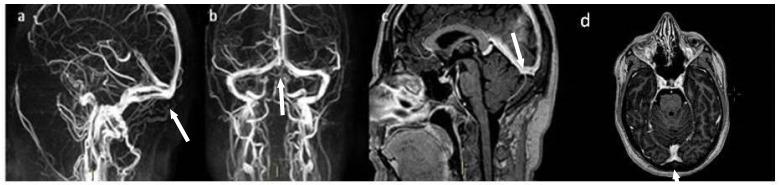

Cerebral venous thrombosis (CVT) is a rare cause of stroke, particularly in young adults. Several known thrombophilic conditions may lead to an increased CVT risk. Interestingly, few cases in the literature have reported an association between CVT and thyrotoxicosis. Here, we describe the case of a young woman with CVT and concomitant thyrotoxicosis, without any other known prothrombotic conditions. We also performed a literature review of CVT cases and hyperthyroidism, searching for all articles published in peer-reviewed journals. We identified 39 case reports/case series concerning patients with CVT associated with thyrotoxicosis, highlighting, in most cases, the association with additional known prothrombotic factors. We then discussed the possible mechanisms by which hyperthyroidism could underlie a pro-coagulative state resulting in CVT. Thyroid disease might be a more common prothrombotic risk factor than expected in determining CVT. However, in most cases, a coexistence of multiple risk factors was observed, suggesting a multifactorial genesis of the disorder. We hope that this work may alert clinicians to consider thyrotoxicosis as a potential risk factor for CVT, even in patients who apparently have no other pro-coagulative conditions.

脑静脉血栓形成(CVT)是一种罕见的中风病因,尤其在年轻人中。几种已知的血栓形成倾向状况可能会增加CVT风险。有趣的是,文献中很少有病例报告CVT与甲状腺毒症之间存在关联。在此,我们描述了一名患有CVT并伴有甲状腺毒症的年轻女性病例,该患者无任何其他已知的血栓前状态。我们还对CVT病例和甲状腺功能亢进进行了文献综述,检索了同行评审期刊上发表的所有文章。我们确定了39例关于CVT与甲状腺毒症相关患者的病例报告/病例系列,在大多数情况下,突出了与其他已知血栓前因素的关联。然后我们讨论了甲状腺功能亢进可能导致促凝状态进而引发CVT的潜在机制。在导致CVT方面,甲状腺疾病可能是一个比预期更常见的血栓前风险因素。然而,在大多数情况下,观察到多种风险因素并存,提示该疾病具有多因素发病机制。我们希望这项工作能提醒临床医生,即使在明显没有其他促凝状况的患者中,也要将甲状腺毒症视为CVT的潜在风险因素。